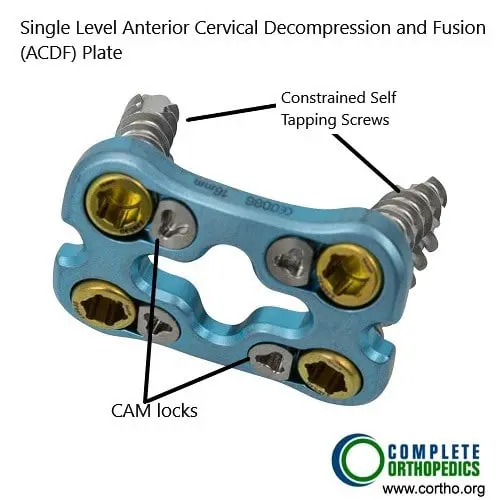

- Anterior cervical discectomy and fusion (ACDF): Removing damaged discs and stabilizing the spine from the front.

ACDF Plate with screws

The images above show a rasp used during the anterior decompression and fusion surgery. The rasp is used to prepare the end plate for insertion of bone cage and subsequent fixation of the vertebrae using the plate shown above.